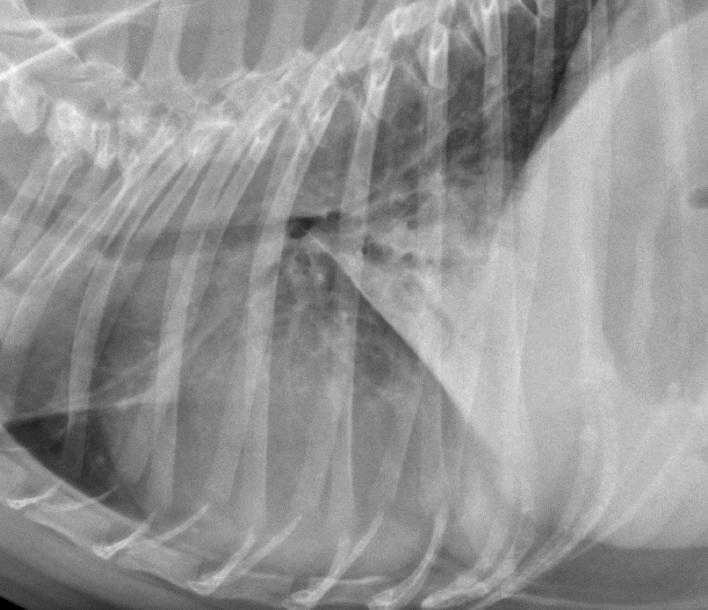

68

Lung Pattern?

Pneumothorax *Arrows = atelectasis*